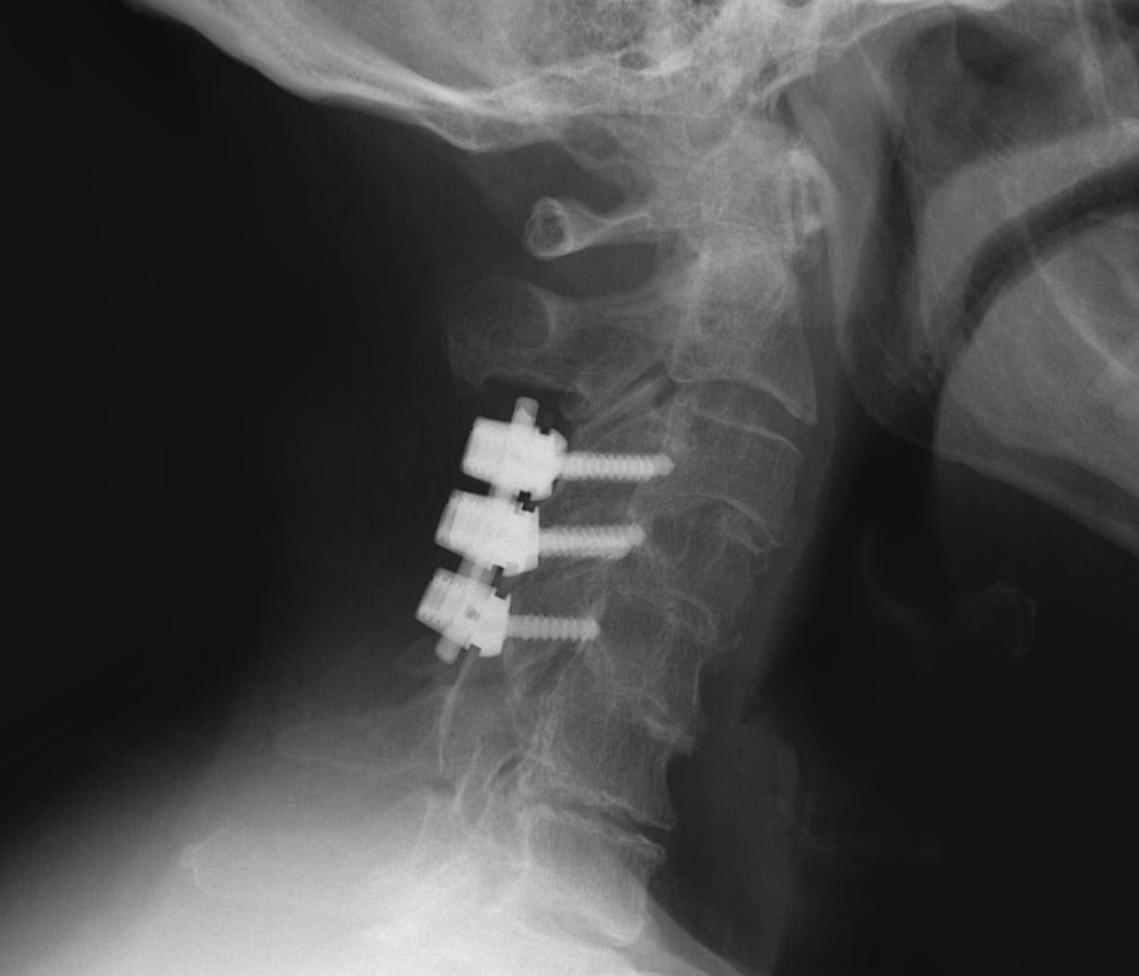

ACDF

Technique

Anterior approach / Smith Robinson

- discectomy

- decorticate end plates

- interbody fusion with bone graft +/- interbody spacer

- anterior low profile plate